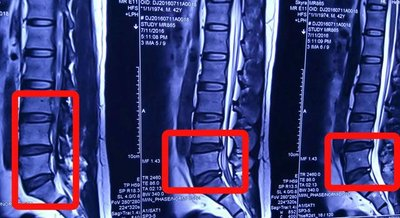

1、急性期:急性期腰椎间盘突出症的治疗首先应用理疗、推拿、针灸、药物缓解肌肉紧张,解除痉挛:然后选用2~3种整复手法,促进突出的椎间盘部分或**还纳,以解除其对神经根的压迫:**通过卧硬板床休息,外用贴剂并配合内服活血化瘀的中药,或静脉滴注右旋糖苷40,以促进神经根炎症、水肿的吸收,消除对神经根的不良刺激,解除症状,恢复功能。全疗程一般需3~7日。

2、慢性期:应选择分离粘连、解除痉挛的方法,如小牵引治疗,然后再用整复手法,不宜首先用直接复位的手法。同时,还应注意并发症的治疗。在恢复阶段注意内服中药,以利于巩固疗效,症状基本消失后可进行康复锻炼,以增强腰部肌肉力量,加强关节结构的牢固性,**消除椎间盘突出的根源,预防复发。

专业治疗:治疗颈椎病、肩周炎、腰椎间盘突出症、膝关节痛、骨质增生症、风湿性**、类风湿**、痛风性**、股骨头坏死、足跟痛等疑难杂症均有良好的疗效。